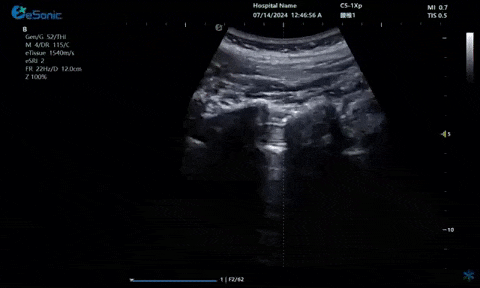

04

超声引导下神经根阻滞,也可以

做腰神经后支

疼痛康复领域中的肌骨超声应用,旨在实现对肌肉、肌腱、韧带、关节、神经、血管、筋膜、滑膜、滑囊、骨膜等组织结构的精确诊断评估。由于超声高频探头对上述机体组织的细微结构具有优异的分辨率,因此能够更为明确地评估这些组织的损伤和炎症状态。同时,超声设备的实时动态评估能力,使得对运动中的相关疾患也能进行准确的评估,这是其他诊断设备所不具备的优势。在康复治疗过程中,肌骨超声还用于介入穿刺治疗,如外周神经阻滞(PNB)、小关节注射、肌筋膜松解术、封闭、小针刀、冲击波治疗等。在超声引导下,这些治疗操作实现了可视化,从而真正意义上实现了精准医疗。以PNB为例,作为一种局部用药方式,其对患者全身干扰小,药物副作用少,且费用较低,因此仍然是临床治疗疼痛的主要方式之一近年来,超声技术在临床康复领域的应用日益凸显其优势。相较于传统的盲穿技术,超声引导下的PNB能够直观显示穿刺和注药过程,无需患者表达异感,避免了反复穿刺给患者带来的痛苦。这种技术显著提高了外周神经阻滞、静脉穿刺的成功率、精确性和安全性,同时减少了不良反应和并发症的发生,为患者带来了福音也相信在不久的将来,eHertz系列产品将会在全球医疗市场上掀起一场技术革新的风暴,让更多的人受益于我国医疗技术的进步。